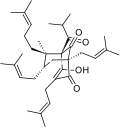

- Natural and semi-synthetic analogues of Hyperforin

-

-

Aristoforin

Aristoforin -

Hyperforin trimethoxybenzoate

Hyperforin trimethoxybenzoate -

Tetrahydrohyperforin

Tetrahydrohyperforin -

Hyperforin nicotinate

Hyperforin nicotinate